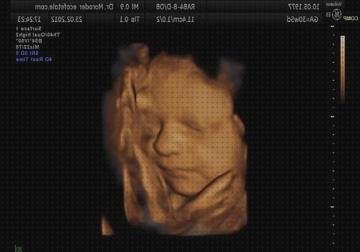

Esta prueba es realizada por un médico que se especializa en hacer e analizar exámenes de diagnosis por imágenes ( radiólogo ) o por un técnico en ecografía (ecografista) que es dirigido por un radiólogo. Esta prueba se hace en la salita de ecografía de un hospital o en el consultorio del doctor.

Deberá tomar todas y cada una de las joyas que pudiesen impedir con la ecografía. Quizá tenga que tomar toda o practicamente todo la ropa, segun la zona que se examine (es posible que le dejen dejarse la ropa interior puesto si las prendas no intervienen en la prueba). Le darán un protector de tela o de papel para que lo use durante el prueba.

Se aplica gel a la piel para hacer más simple el paso de las ondas de sonido. Se pone el transductor en el gel y se está moviendo sobre la piel. Usted debe de durar muy parado a lo largo del método. Podría disfrutar sonidos que representan el flujo de sangre a través de los vasos sanguíneos.